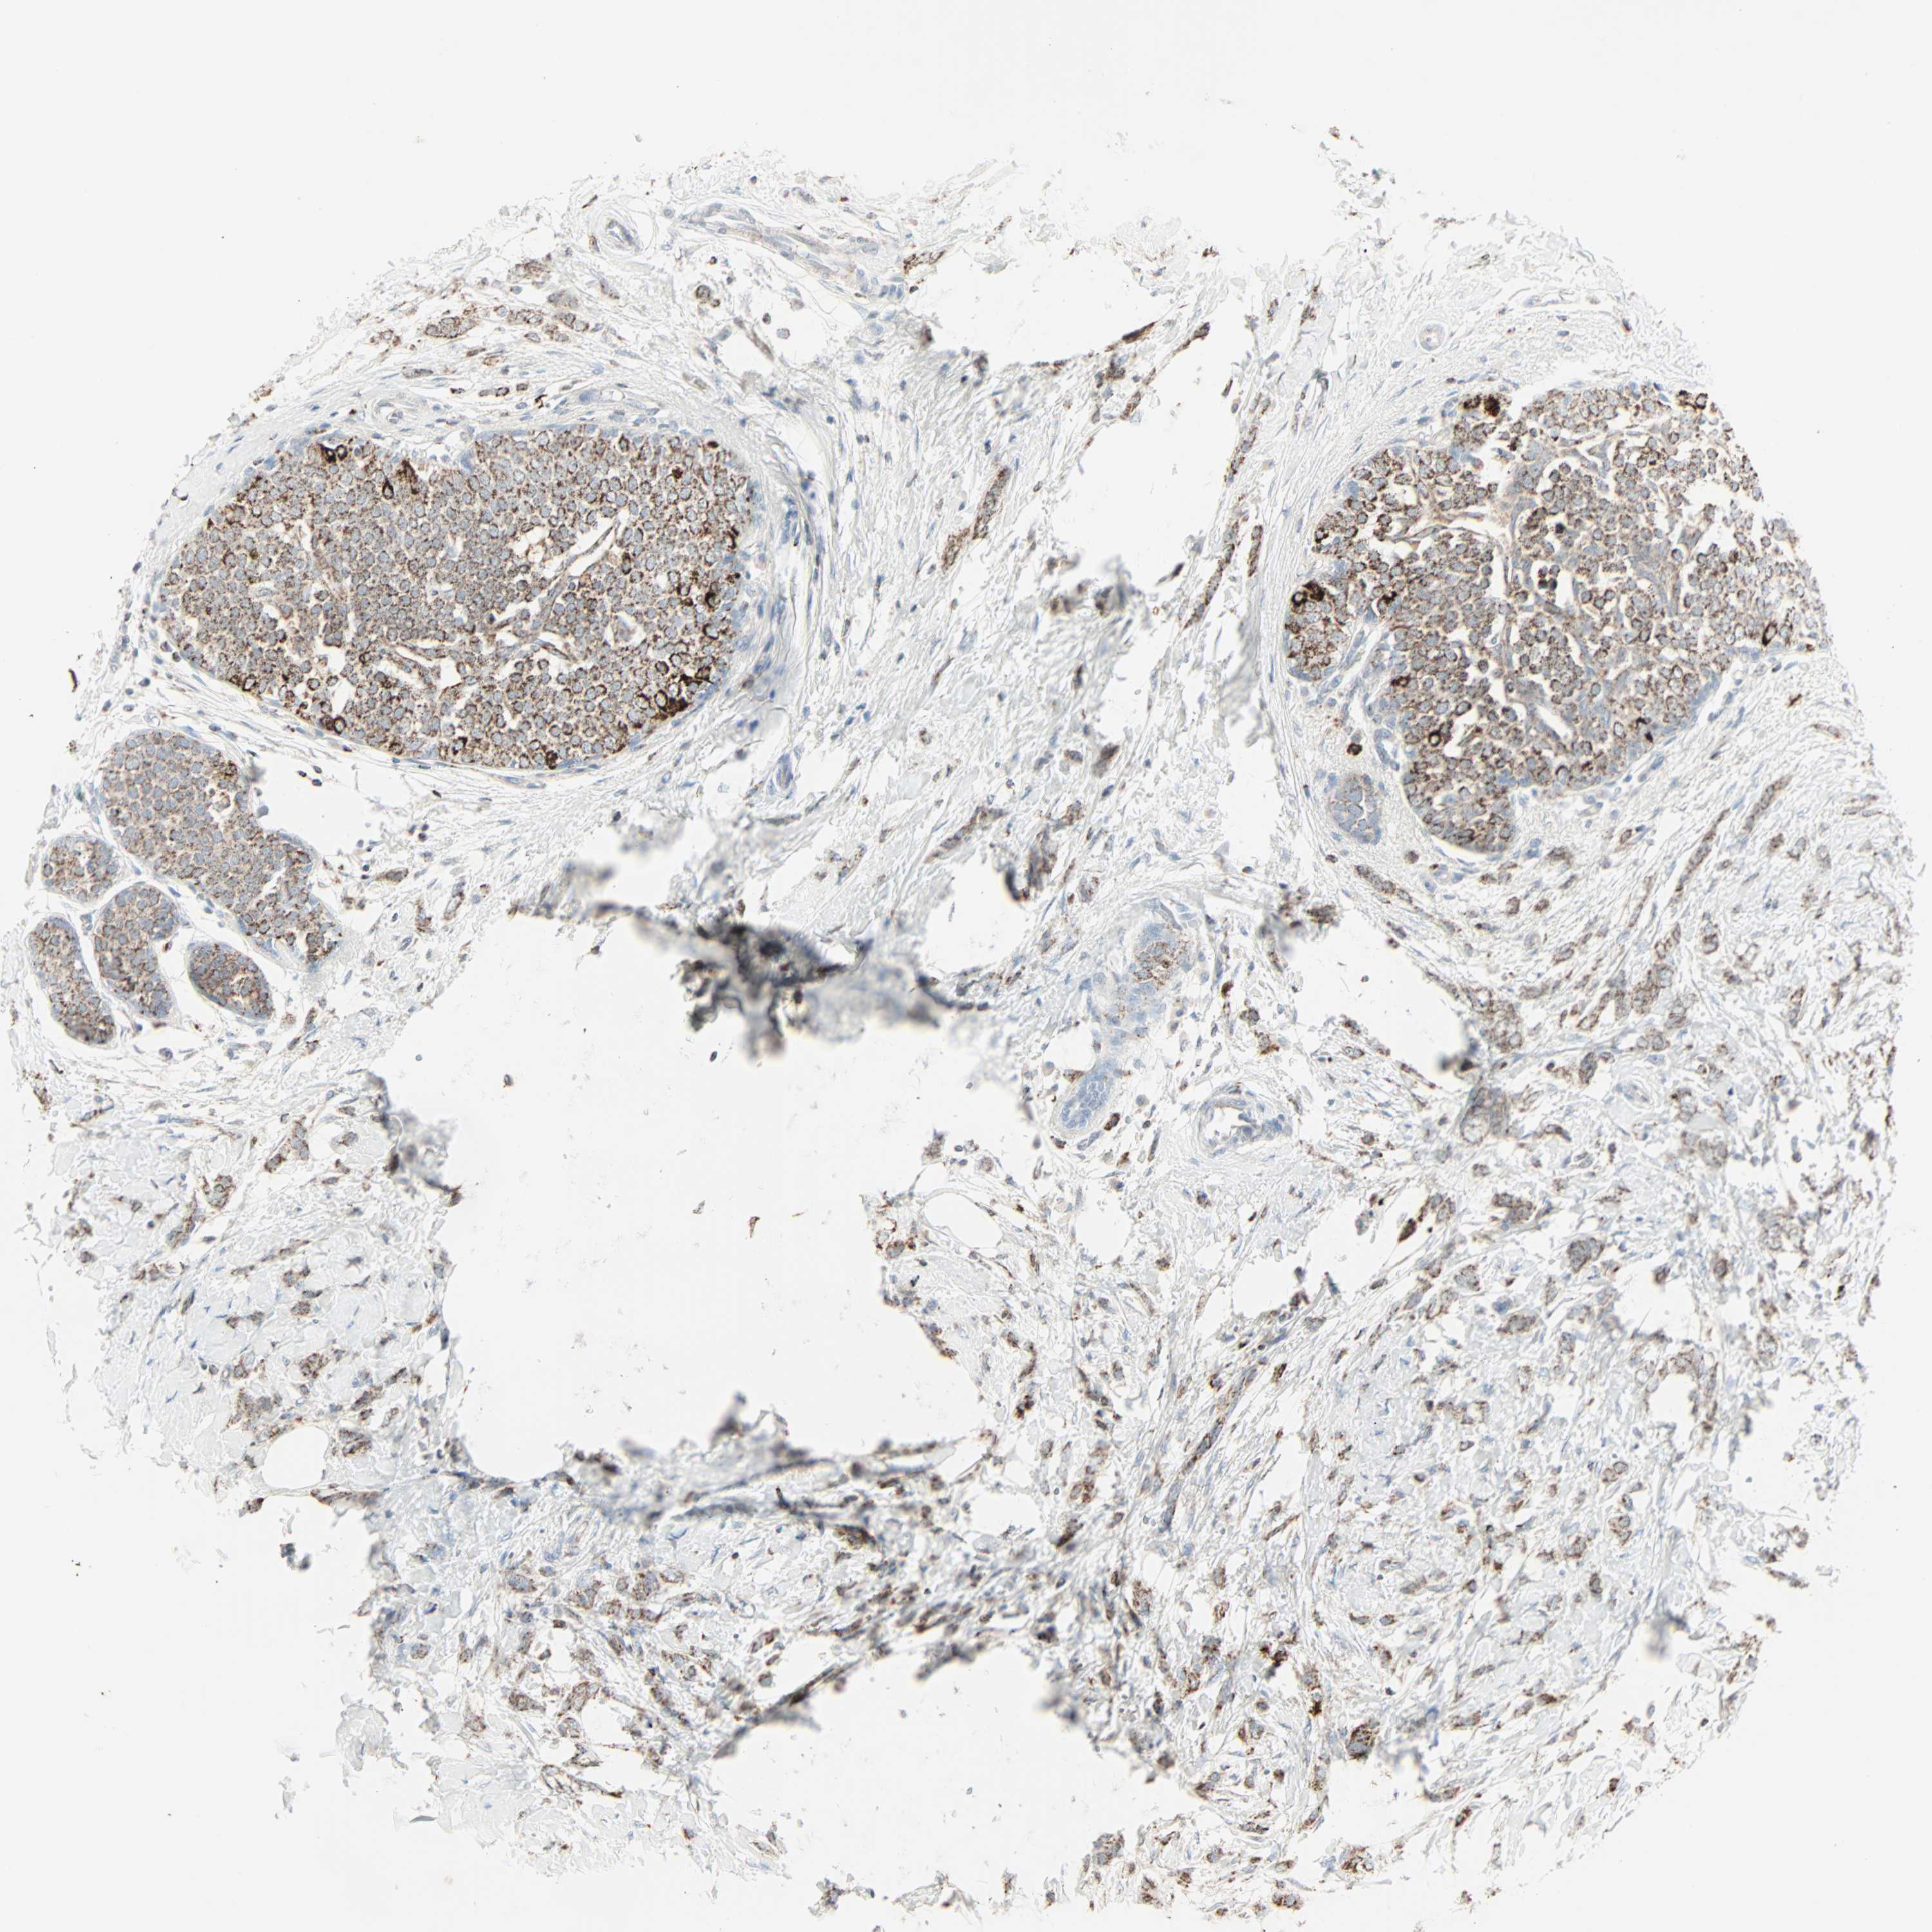

CANCER BREAST CANCER Show tissue menu

Breast cancer

Human cancer